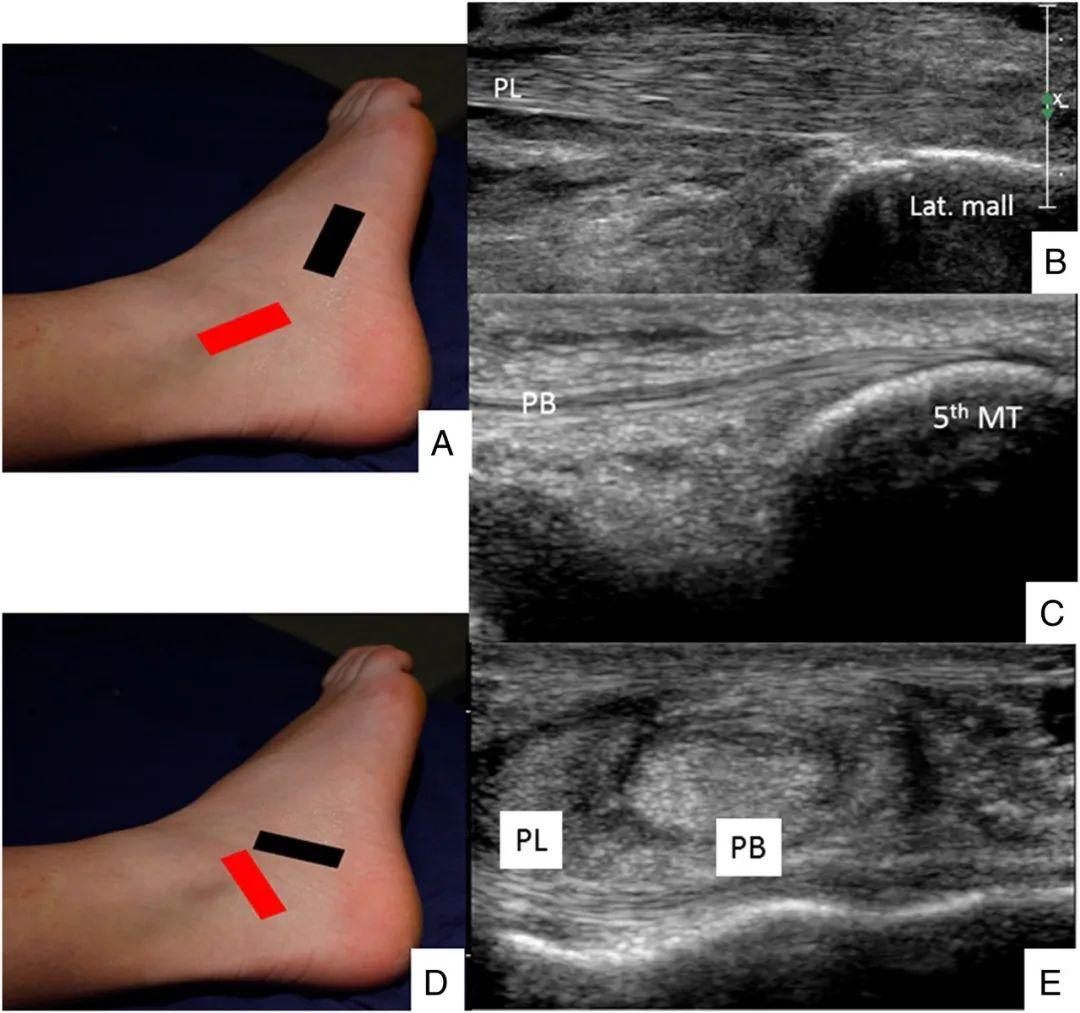

超声在足踝部检查中的应用

图片尺寸898x645

图片尺寸918x640